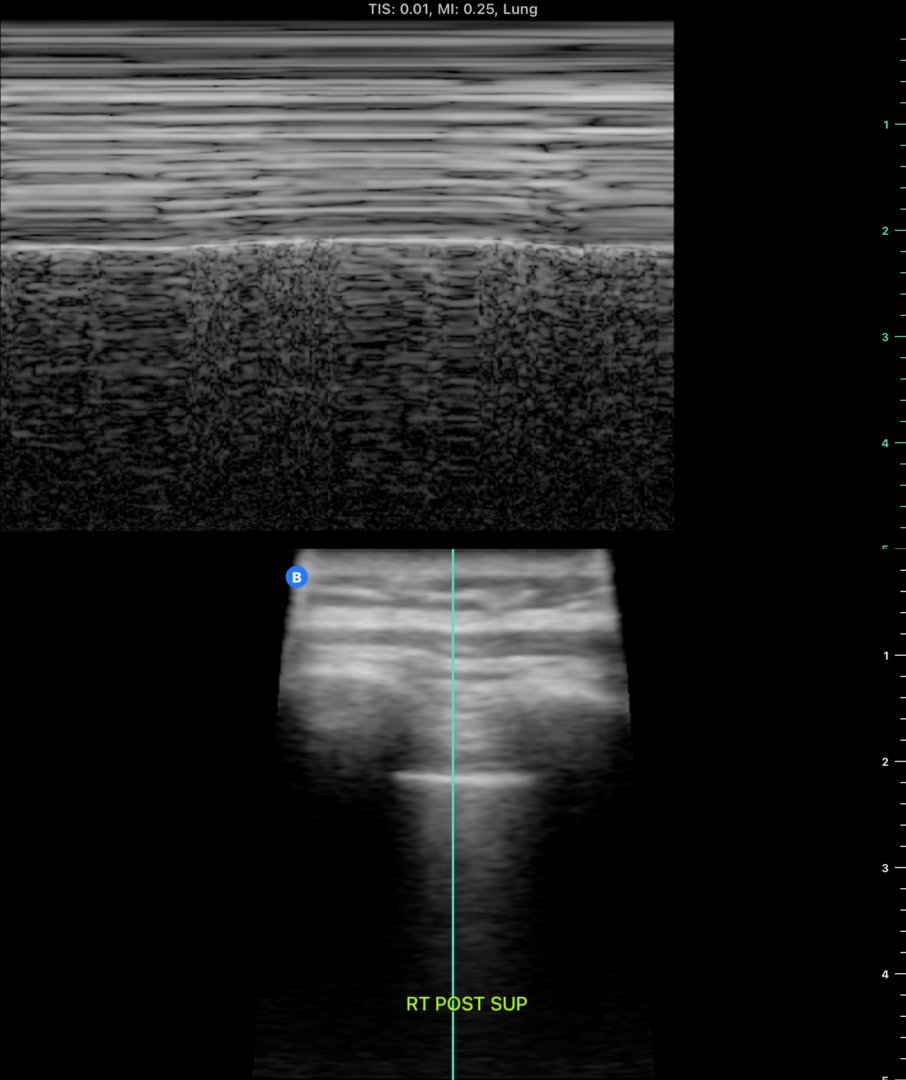

5/ While waiting for CXR, #POCUS was performed to assess for lung sliding.

Left posterior superior view:

Upon viewing multiple other spots, unable to find an actual lung point but do confirm absence of lung sliding in the middle of the left lung.

So why the absent lung sliding??

This is an excellent example of the limitations of lung sliding for evaluating for PTX. Absence lung sliding is sensitive but NOT specific - many things can cause absent lung sliding, including a large mass on the pleura, like in this case.

Lung point, however, is far more specific for PTX but this was not found in this case. (thanks @pocus101)